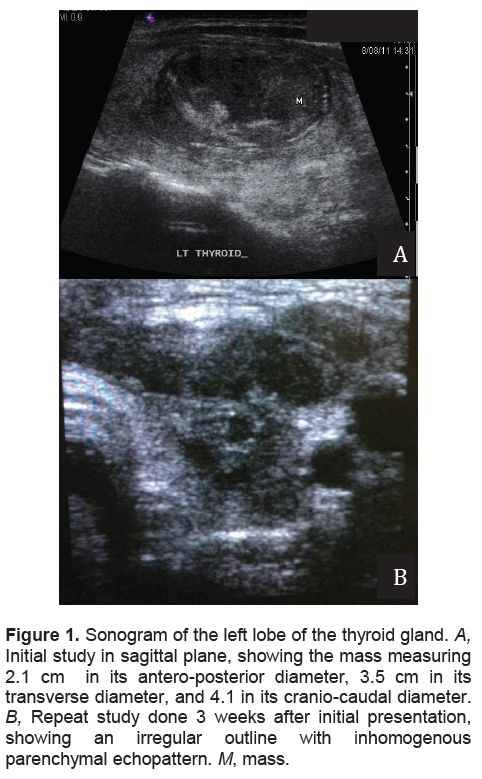

Her complete blood count was normal, with an erythrocyte sedimentation rate (ESR) of 18mm/hr. Thyroid function tests showed slightly suppressed TSH with normal FT4. Thyroid ultrasonography revealed multiple bilateral nodules, with a dominant, solid, inhomogeneous mass occupying almost the entire left lobe (Figure 1A). Thyroid scintigraphy using I-131 showed a poorly visualized thyroid gland with low 2-hour and 24-hour radioactive iodine uptake (RAIU) values consistent with thyroiditis.

On a follow-up visit after 3 weeks, a yellowish discharge was noted in the center of fluctuant swelling with surrounding erythema overlying the skin (Figure 2A). A thyroid sonogram performed at the Endocrine Center of our institution showed that the left lobe of the thyroid had an irregular outline with inhomogenous parenchymal echopattern (Figure 1B

).She was referred to Otorhinolaryngology for incision and drainage of the midline neck abscess. Repeat FNA was uninformative yielding only purulent material. The abscess was then unroofed and drained. Purulent material continued to exude through the sinus at the center of the swelling. A contrast-enhanced computerized tomography (CT) scan of the neck was performed to rule out branchial cleft anomalies. The scan revealed an irregular inhomogeneous soft tissue structure measuring 3.0 cm x 3.4 cm x 2.8 cm with an area of hypodensity suggestive of infective fluid collection above and extending into the thyroid lobe (Figure 3A and 3B). Fistulogram showed a subcutaneous blind-ended pouch with contrast pooling, suggestive of an abscess cavity. No fistulous tract into the pyrifrom sinus or other pharyngeal structures was appreciated (Figure 4). Several courses of oral antibiotics were prescribed during the succeeding weeks but without apparent resolution of symptoms. The lists of antibiotics were: cefixime 200mg tablet every 12 hours for 7 days; ampicillin/sulbactam 750 mg tablet every 8 hours for 14 days plus clindamycin 300 mg tablet every 6 hours for 7 days.

Figure 1. Sonogram of the left lobe of the thyroid gland. A, Initial study in sagittal plane, showing the mass measuring 2.1 cm in its antero-posterior diameter, 3.5 cm in its transverse diameter, and 4.1 in its cranio-caudal diameter. B, Repeat study done 3 weeks after initial presentation, showing an irregular outline with inhomogenous parenchymal echopattern. M, mass.